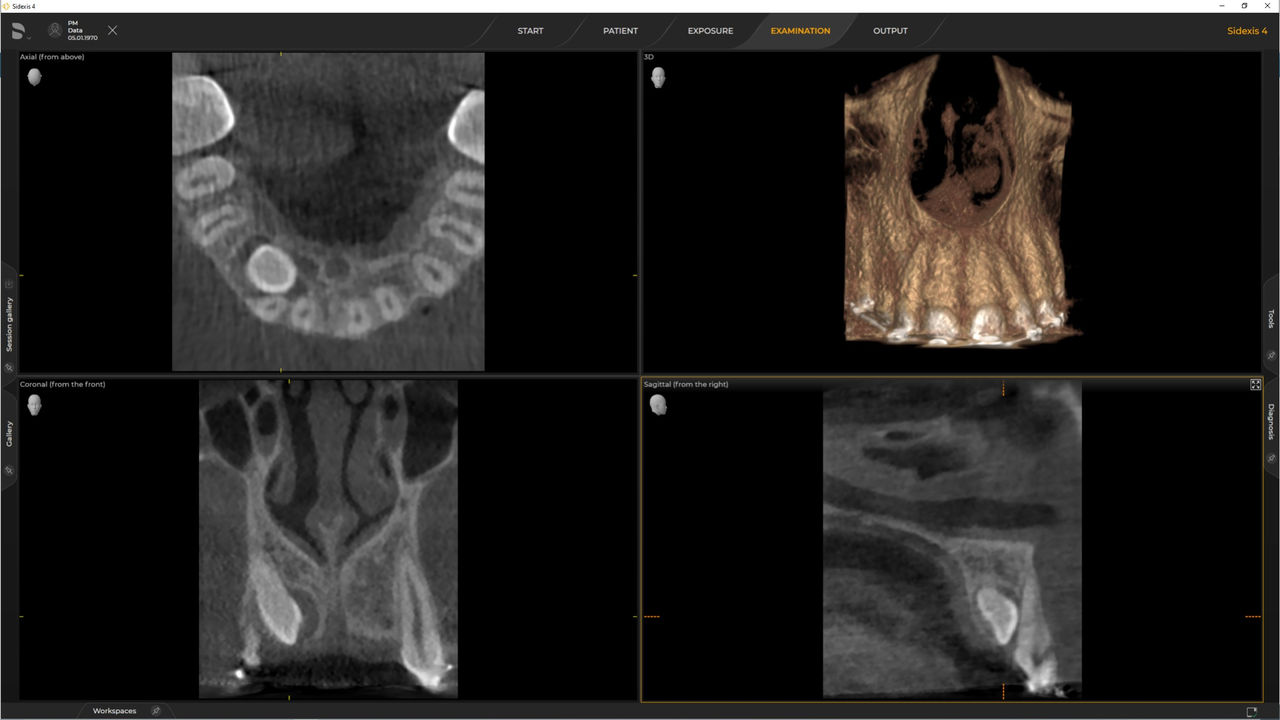

Con el modo de dosis baja inteligente 3D, obtiene imágenes 3D en el rango de dosis de una imagen radiológica 2D. En el modo HD (hasta 1400), las imágenes individuales se obtienen durante una única rotación y se convierten en un volumen 3D con hasta 80 μm para imágenes de bajo ruido en alta resolución.

Las unidades de radiología de Dentsply Sirona funcionan exclusivamente con Sidexis 4. Sin embargo, la migración de datos de Sidexis XG a Sidexis 4 es muy fácil. Sidexis 4 permite una experiencia digital completa con las últimas herramientas